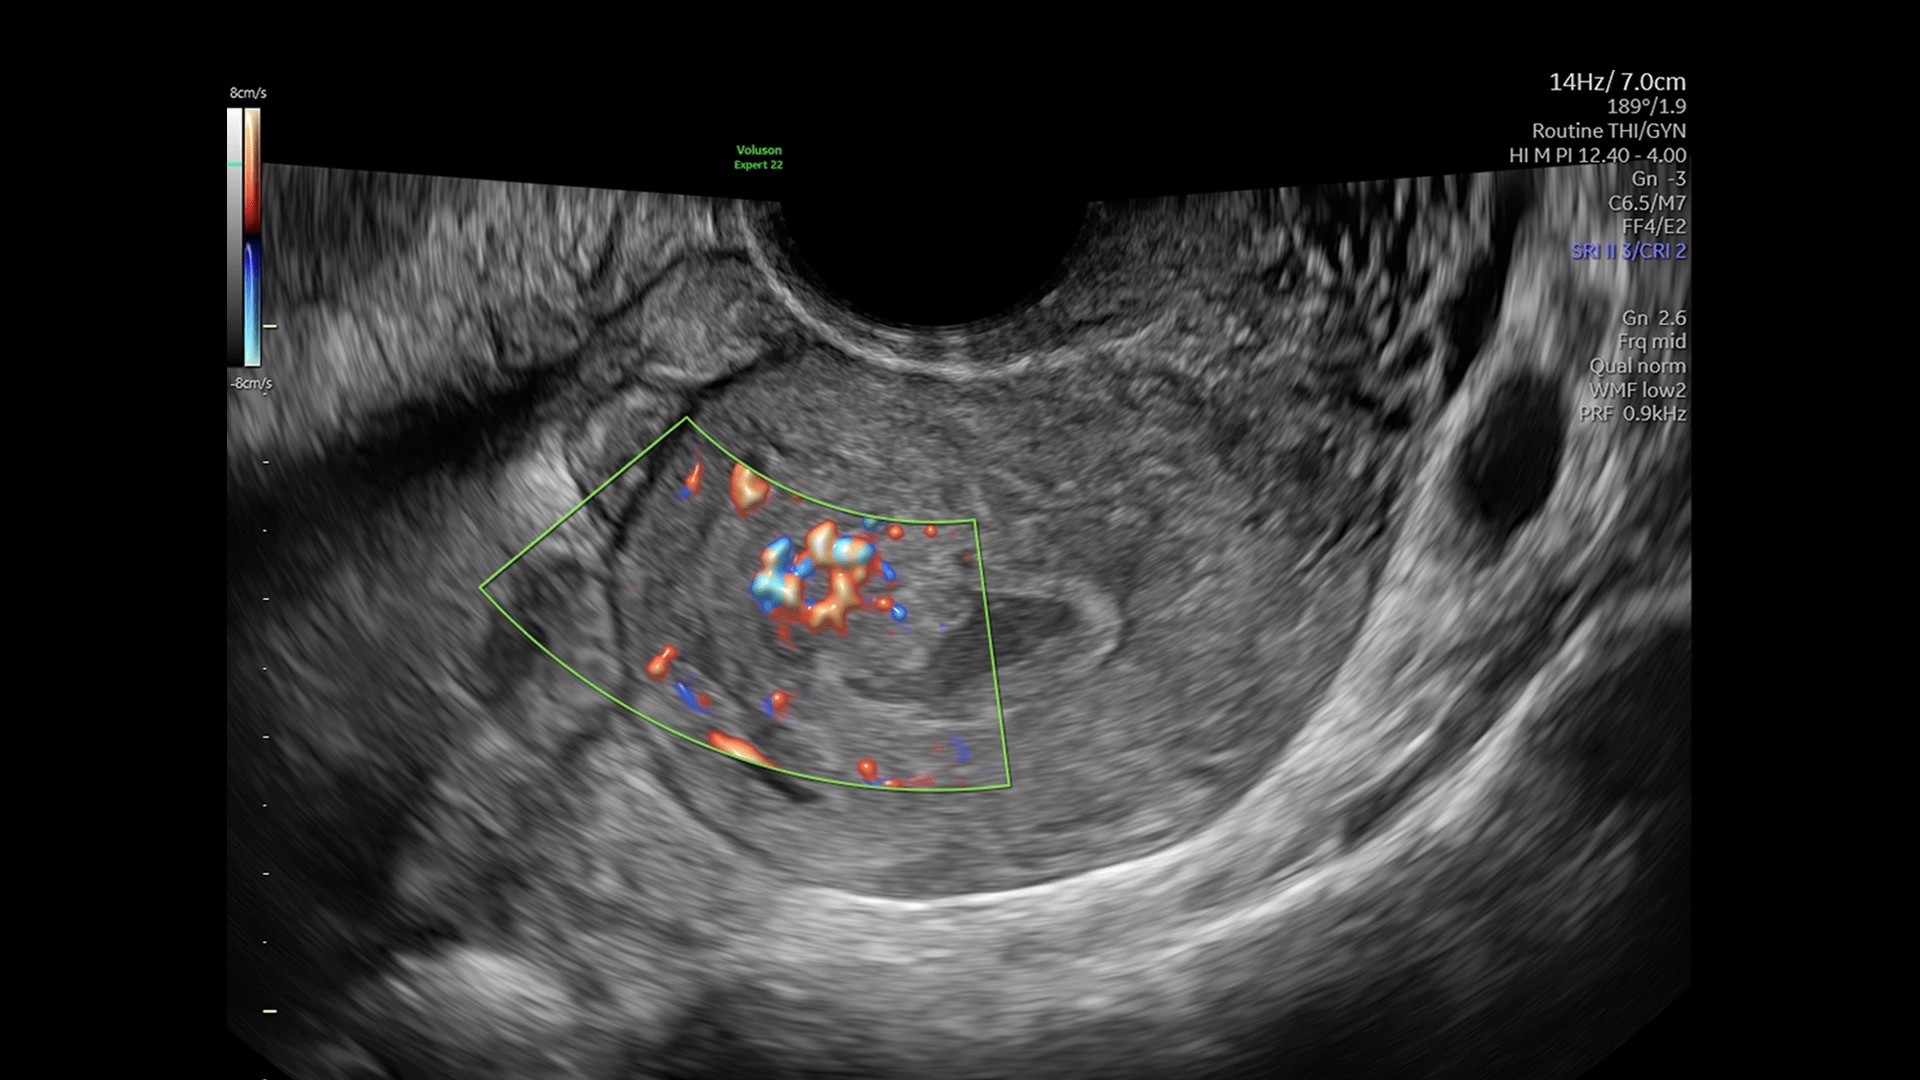

Doppler imaging

Beyond Basic Blood Flow

Voluson is pushing imaging boundaries to make blood flow assessment faster and easier. Our advanced technologies, including Graphicflow, Radiantflow, Slowflow, and Radiant imaging, increase resolution and sensitivity in color and pulsed wave Doppler for unprecedented clarity